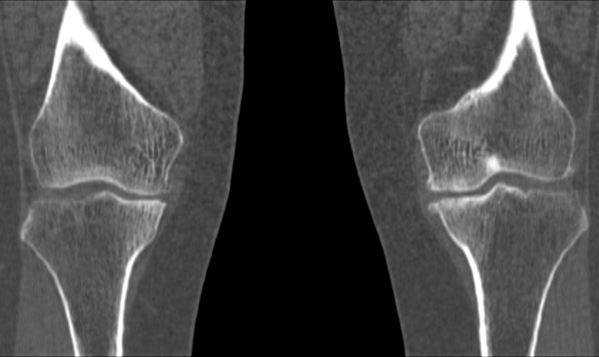

Фото томографии коленных суставов

Фото МСКТ коленного сустава в первую очередь показывают кости (бедренную, мало- и большеберцовую, надколенник). Также на снимках можно увидеть:

внутри- и внесуставные связки.

МСКТ коленного сустава (коронарная проекция)

Стандартные проекции, применяемые при рентгенографии коленного сустава - прямая (передне-задняя) и боковая (рис.1). По мере необходимости их дополняют правой или левой косой, а также аксиальной проекциями. Основным правилом при рентгенологическом исследовании коленного сустава является полипозиционность.

Эффективность рентгенодиагностики повреждений коленного сустава напрямик зависит от качества рентгенограмм, критериями которого являются:

- в прямой проекции:

- симметричность аксиальных сторон обоих мыщелков бедренной кости;

- расположение межмыщелковых возвышений по центру межмыщелковой ямки;

- частичная маскировка головки малоберцовой кости метаэпифизом большеберцовой кости (примерно на 1/3 своего поперечного размера);

- наложение контуров надколенника на центральную область метаэпифиза бедренной кости;